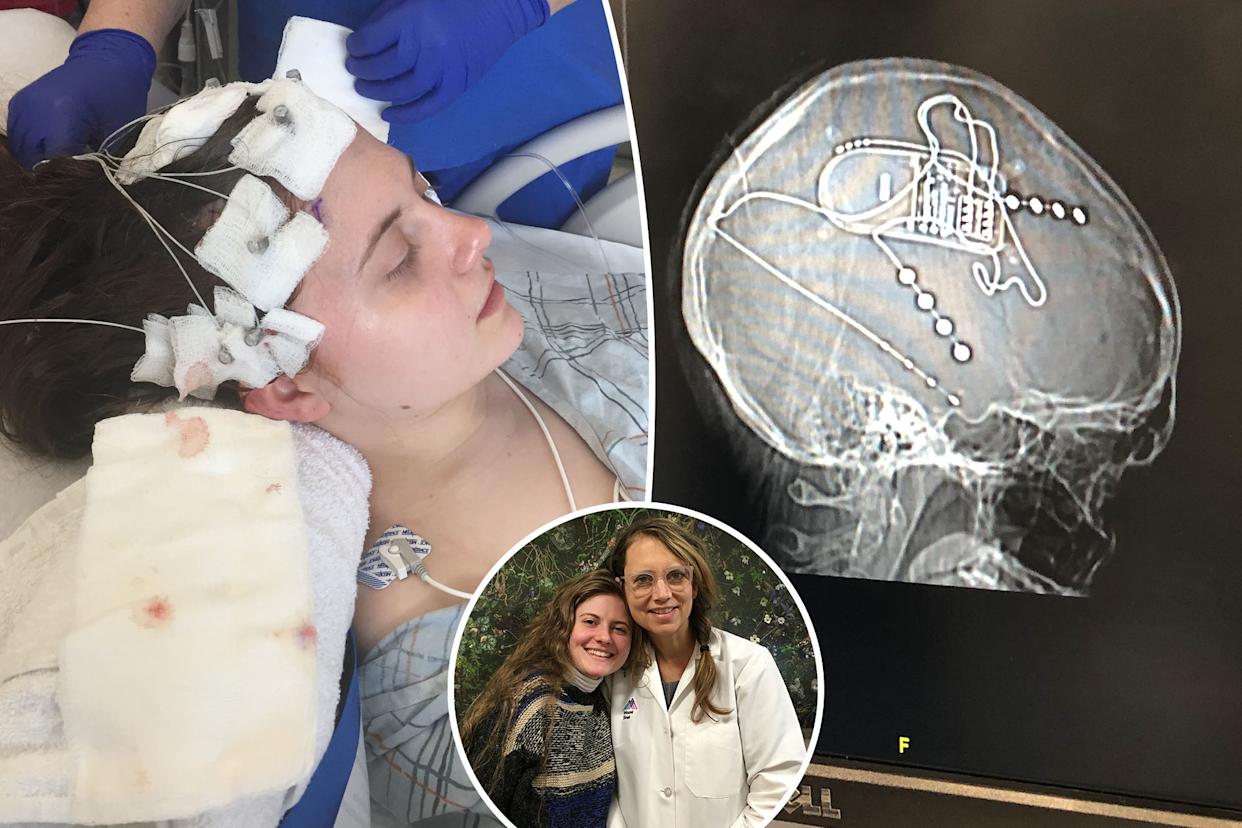

Arielle Hoffman was just 22 years old when she began experiencing strange episodes that altered her consciousness. Courtesy of Arielle Hoffman

Courtesy of Arielle Hoffman

Hoffman and her neurologist, Dr. Lara Marcuse. Courtesy of Arielle Hoffman

Hoffman underwent stereoelectroencephalography to pinpoint where her seizures were starting in the brain. Courtesy of Arielle Hoffman